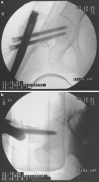

This study is a randomized prospective study comparing two fracture fixation implants, the extramedullary sliding hip screw (SHS) and the dual lag screw cephalomedullary nail, in the treatment of intertrochanteric femoral fractures in the elderly. One hundred and sixty-five patients with low-energy intertrochanteric fractures, classified as AO/OTA 31A, were prospectively included during a 2-year period (2005-2006). Patients were randomized into two groups: group A included 79 hip fractures managed with sliding hip screws and group B included 86 fractures treated with cephalomedullary nails. Delay to surgery, duration of surgery, time of fluoroscopy, total hospital stay, implant-related complications, transfusion requirements, re-operation details, functional recovery, and mortality were recorded. The mean follow-up was 36 months (24-56 months). The mean surgical time was statistically significantly shorter and fluoroscopy time longer for the group B. No intraoperative femoral shaft fractures occurred. There was no statistically significant difference in the functional recovery score, reoperation, and mortality rates between the 2 groups. A new type of complication, the so-called Z-effect phenomenon, was noticed in the cephalomedullary nail group. There are no statistically significant differences between the two techniques in terms of type and rate of complications, functional outcome, reoperation and mortality rates when comparing the SHS and the cephalomedullary nail for low-energy AO/OTA 31A intertrochanteric fractures. Our data do not support recommendations for the use of one implant over the other.